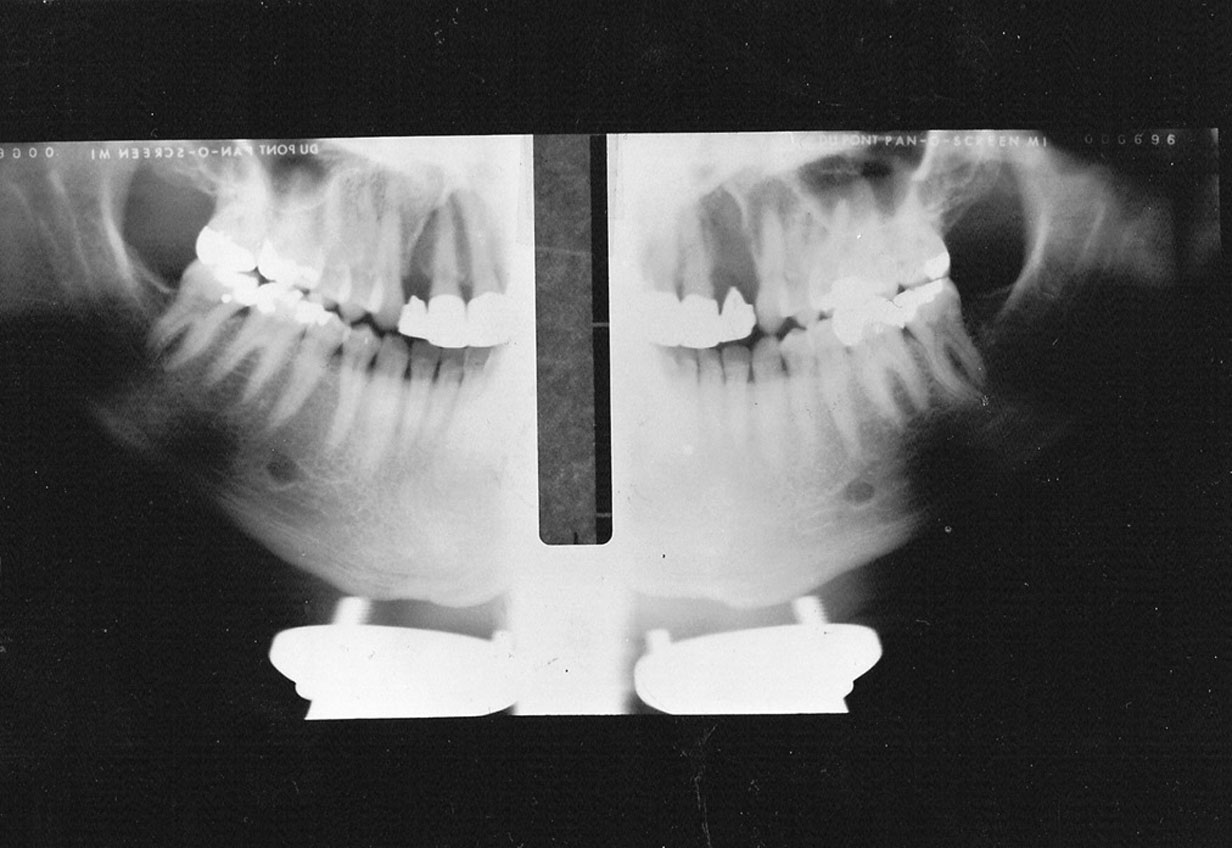

Vertical Height

If the patient’s head is positioned too high, or if the film cassette and tubehead are too low, the superior part of the condyles of the ramus and much of the maxilla will be missing from the film, as in Figure 20. In the reverse situation, if the patient’s head is too low, or the cassette and tubehead are too high, the lower border of the mandible will be lost.

Figure 20. Vertical height.

Figure 20